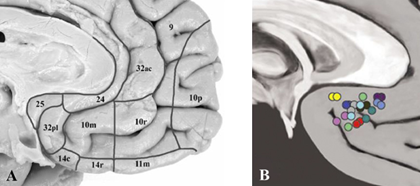

抑郁症的主要临床表现为情绪低落、快感缺失等其他认知、生理以及行为症状。已有研究表明(Huang et al., 2019, The Lancet Psychiatry),截止到2015年,我国抑郁症的终身患病率为6.9%,12个月患病率为3.6%;在655名成年人抑郁症群体中,18-34岁占比17%,35-49岁占比30%,50-64岁占比37%,65岁以上占比16%。抑郁症作为一种脑疾病,深部脑刺激技术常用来治疗难治性抑郁,胼胝体下部的扣带回区域(Subcallosal Cingulate Gyrus, SCG)是常见的刺激靶点。SCG是腹侧扣带回的一部分,主要包括Brodmann 25区和部分Brodmann 24和 32区,位于胼胝体下部(见图1)。SCG与边缘系统联系紧密,常与杏仁核、海马,纹状体等区域一起参与自主调节、情绪调节、自传体记忆和奖励学习相关的认知过程。

图1. SCG区域结构展示图(A)和深部脑刺激刺激靶点(B). 图片来源(Hamani et al., 2011, Biological Psychiatry)